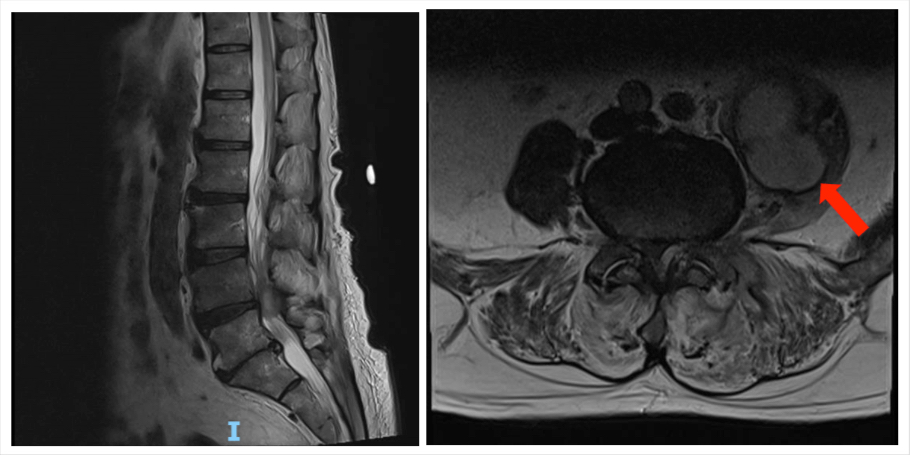

Although the patient was clinically stable, afebrile and infection markers were relatively unchanged in subsequent blood tests (see Table 1), the pain did not subside with opioids analgesia and physiotherapies. Hence, MRI lumbar spine was performed on Day 13 of admission due to the change in the pain character, poor response to analgesia and functional decline. Left facet joint septic arthritis, left para-facet joint abscess and left psoas abscess were investigated on MRI scan (Figure 1). The patient denied invasive surgical interventions. Therefore, he underwent CT-guided drainage of abscesses followed by 6weeks of intravenous Penicillin G, which was targeted antibiotic therapy based on the culture of the abscess drain sample, which grew Streptococcus agalactiae and analgesia. No other suspicious infection source or mass was found in the CT scan of the abdomen and pelvis and echocardiogram. A repeated MRI scan in 6 weeks showed the complete resolution of infection. The patient was discharged successfully with dramatic improvement in pain and mobility after rehabilitation.

Figure 1. MRI of lumbo-sacral spine showing left facet joint septic arthritis complicated by a 2.4cm left para-facet joint abscess and a 5.1cm left psoas abscess with the extension of the abscess into the L4 and L5 epidural spaces (Red arrow showing psoas abscess)